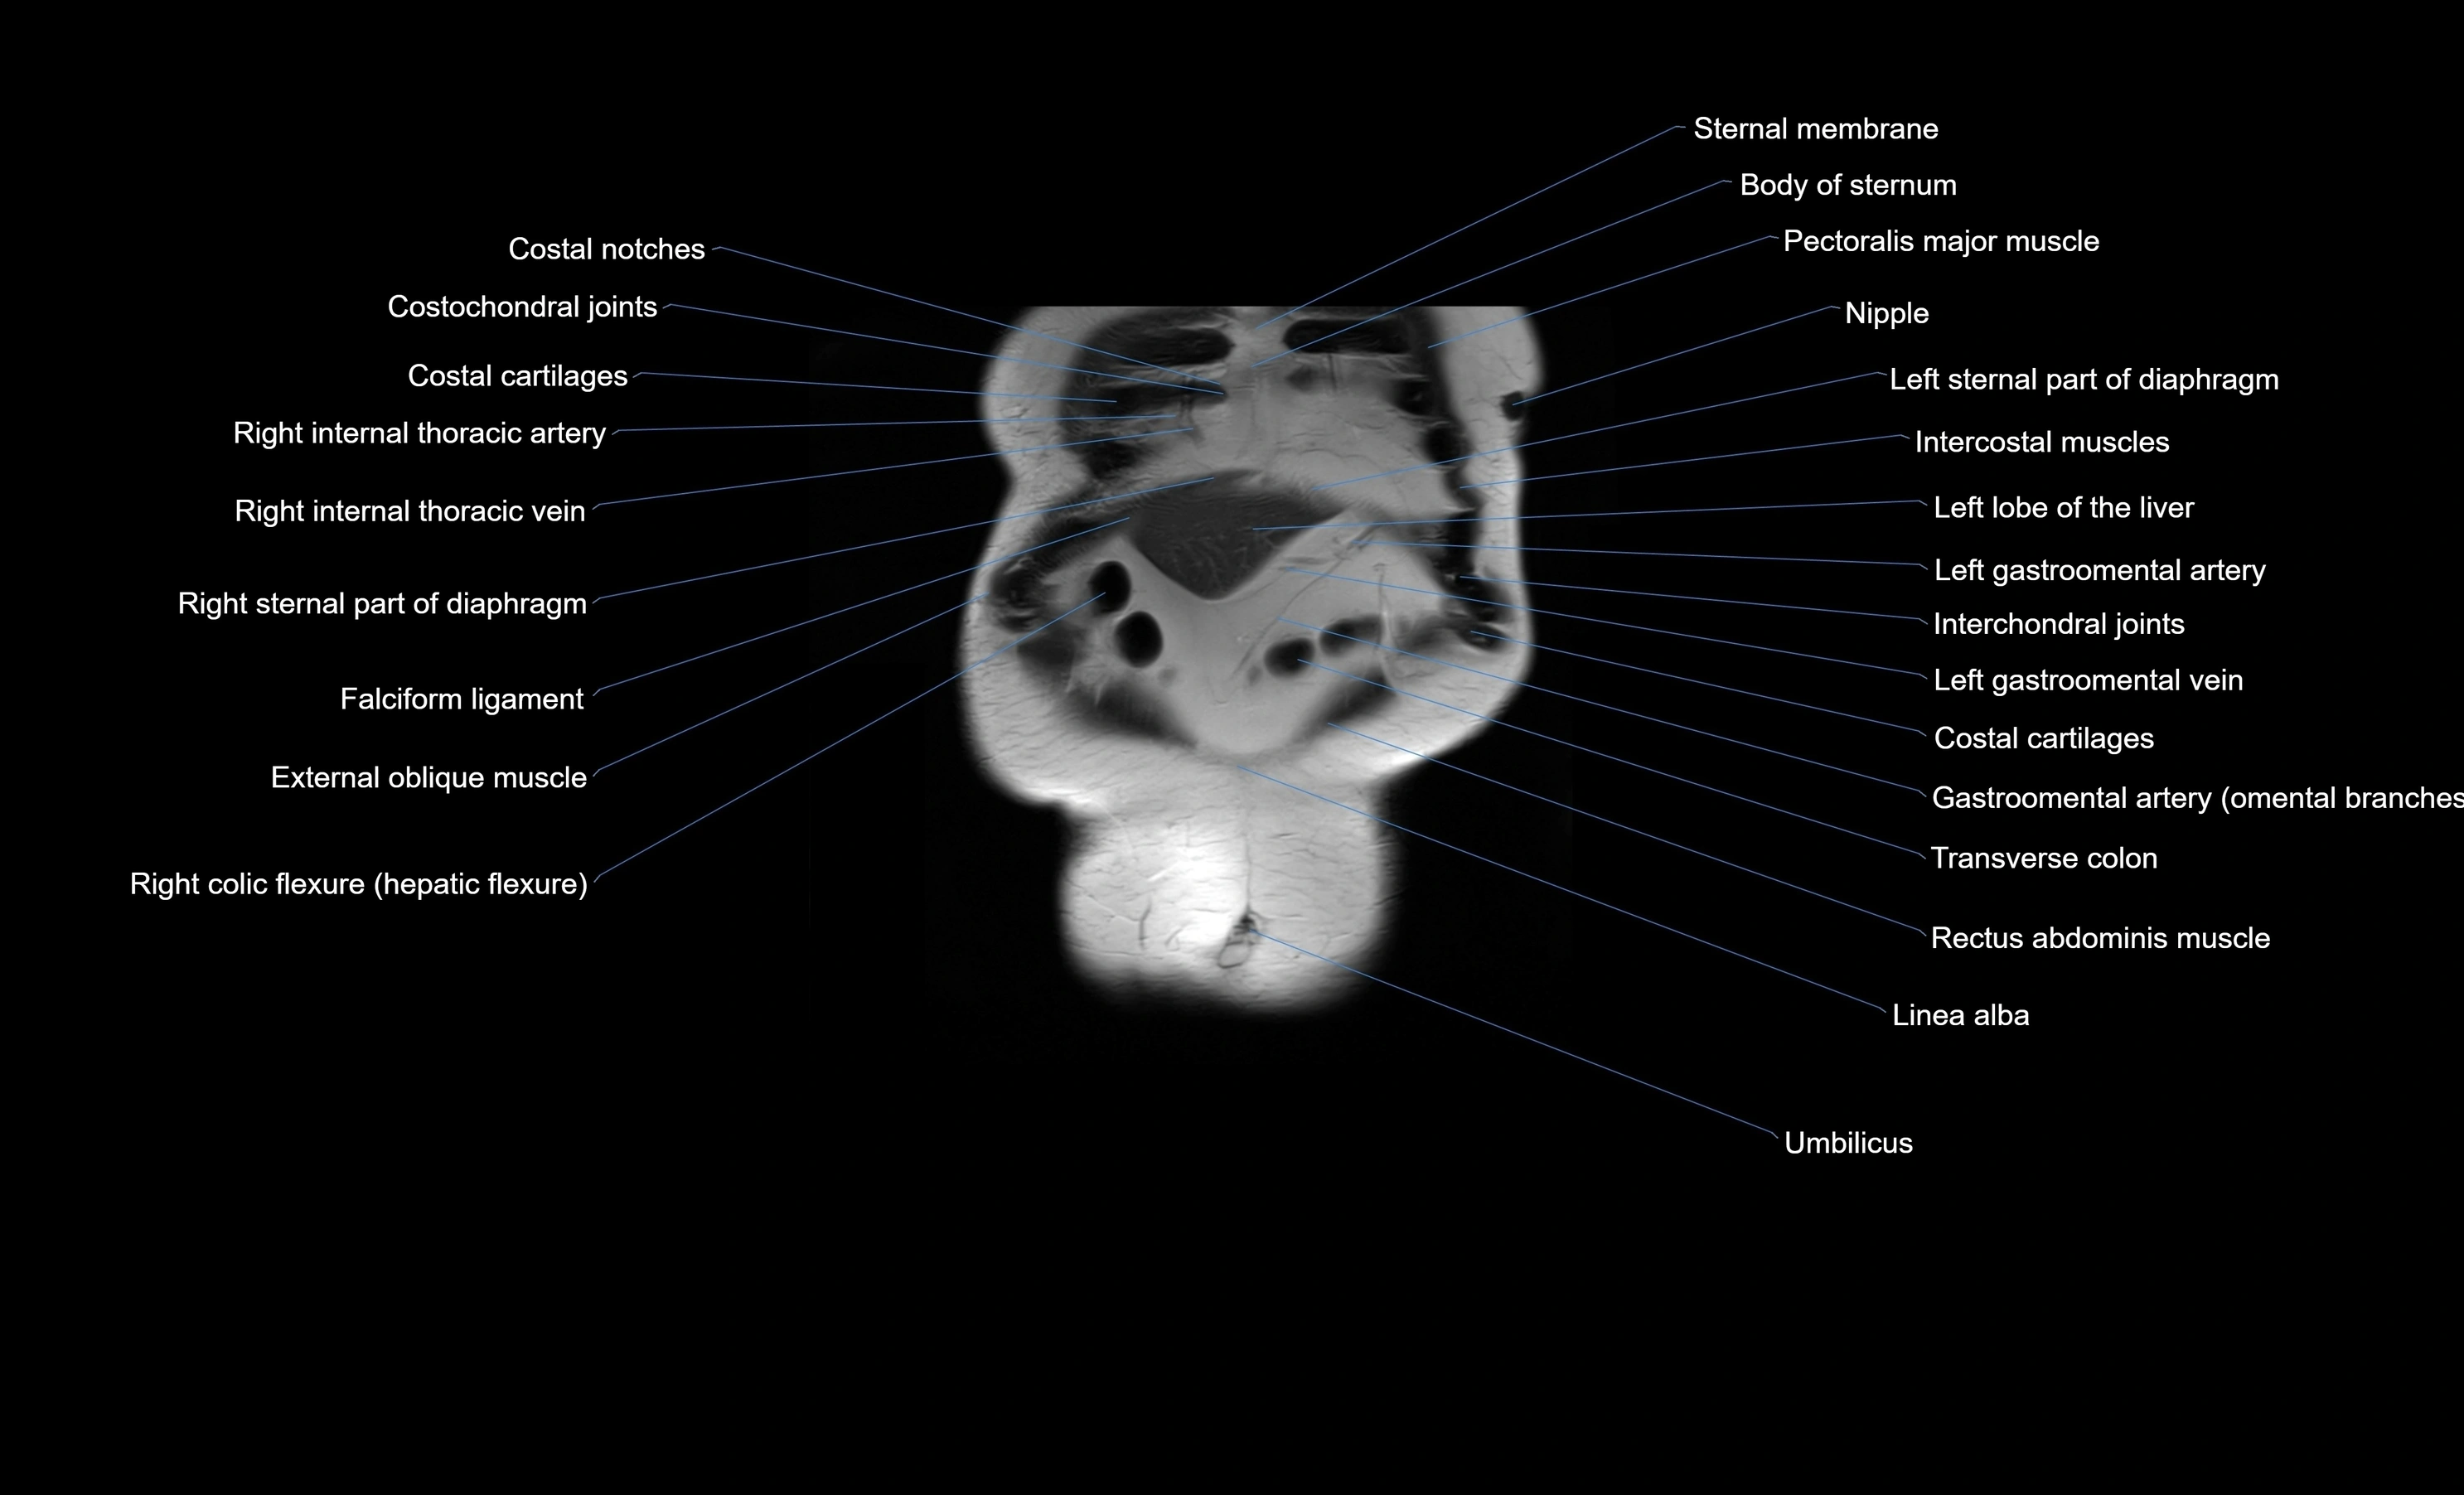

MRI images